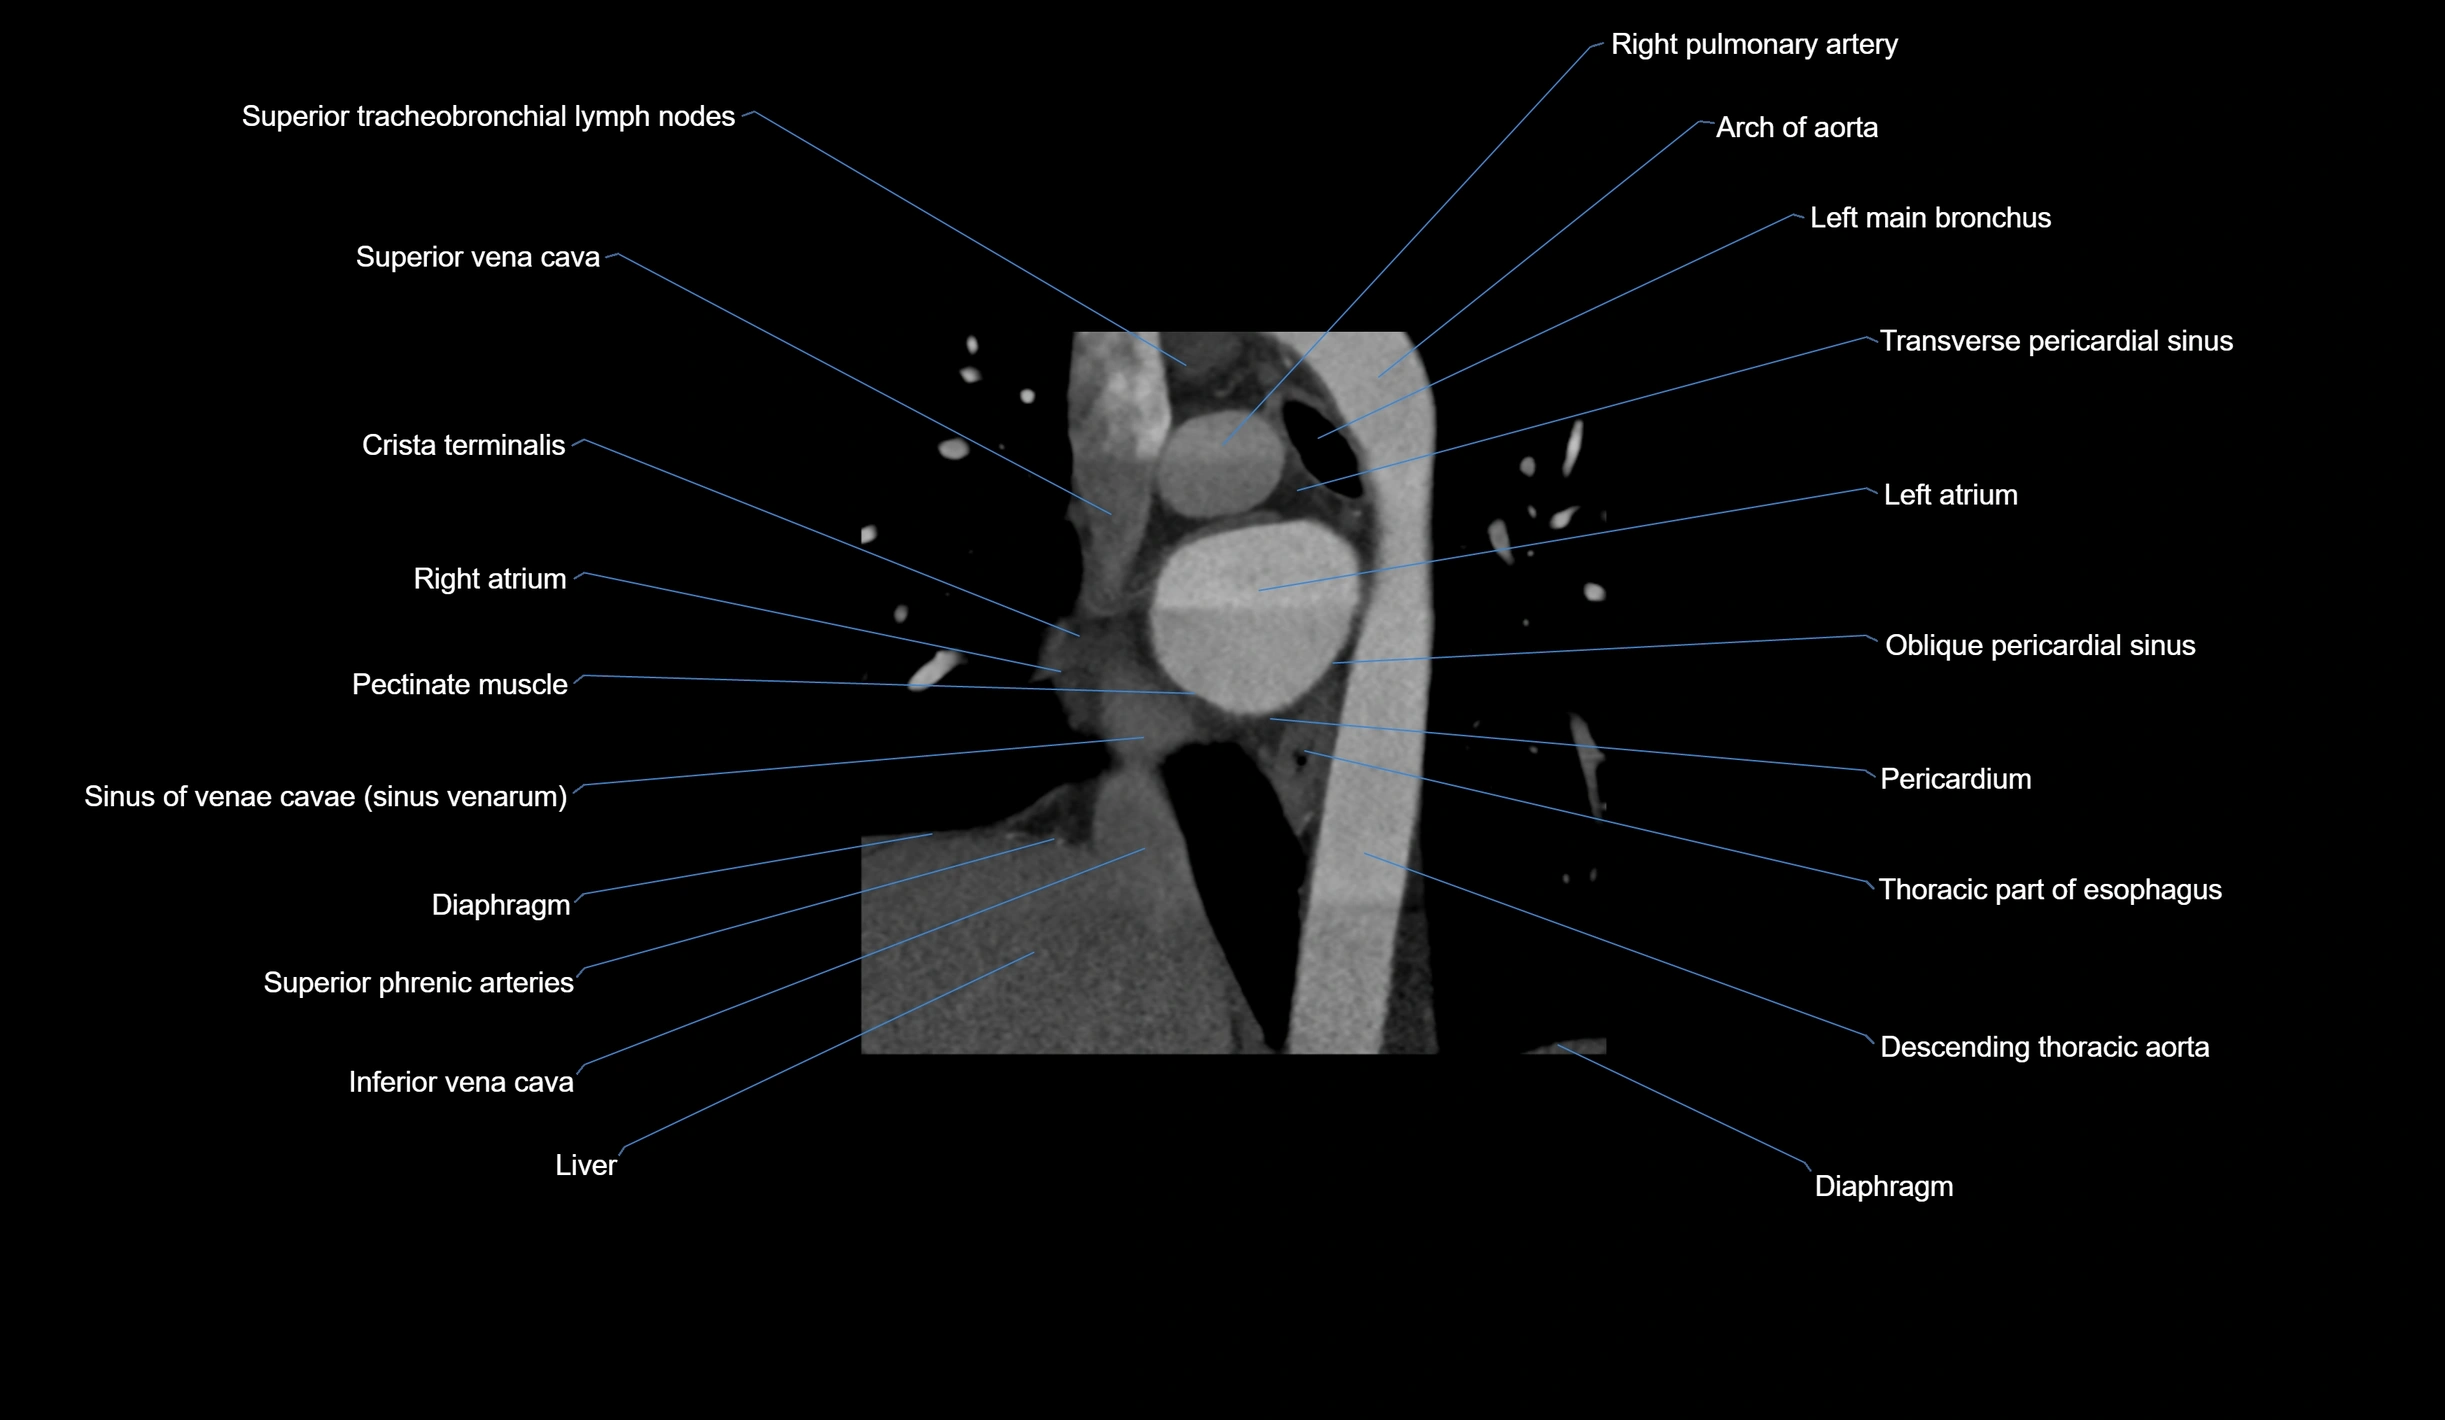

CT images